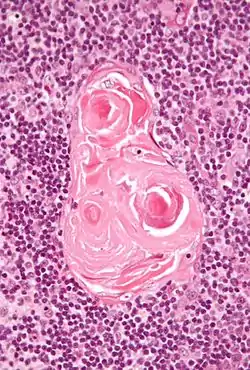

In the medulla, the network of epithelial cells is coarser than in the cortex, and the lymphoid cells are relatively fewer in number.[1] Concentric, nest-like bodies called Hassall's corpuscles (also called thymic corpuscles) are formed by aggregations of the medullary epithelial cells.[3] These are concentric, layered whorls of epithelial cells that increase in number throughout life.[1] They are the remains of the epithelial tubes, which grow out from the third pharyngeal pouches of the embryo to form the thymus.[5]

Micrograph showing a Hassall's corpuscle, found within the medulla of the thymus.